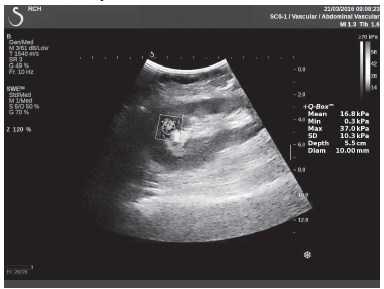

Клинический пример из второй группы. Пациент К. перенес операцию пересадки почки от живого родственного донора. Трансплантат в левой подвздошной области. Индекс резистентности в междольковых артериях составил 0,70 (рис. 5). В сегментарных артериях индекс резистентности составил 0,66 (рис. 6). Показатели жесткости паренхимы почечного трансплантата при режиме УЭСВ составили от 31,6 до 36,9 кПа (рис. 7-9).

Рисунок 7. Исследование в режиме ультразвуковой эластографии сдвиговой волны у пациента К.: жесткость паренхимы в зоне медиального края почечного трансплантата 36,9 кПа